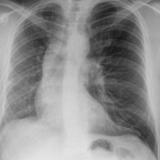

Bronchial atresia

Date: 03/29/2014

Views: 3251